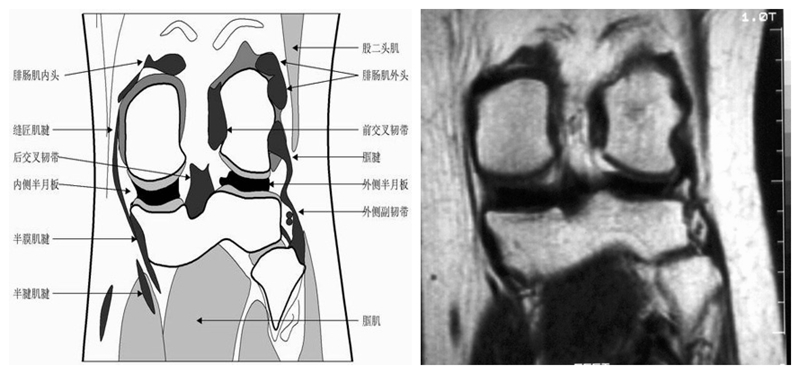

膝关节冠状面MRI解剖

显示内外侧副韧带、腘肌和拱状韧带,有无信号和结构改变,侧重关节胫股软骨的两边和半月板的体部。

冠状位解剖第二层